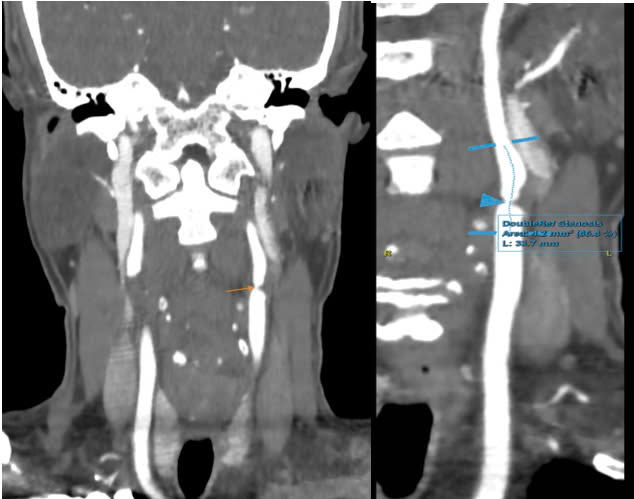

Chưa dừng lại ở đó, hình ảnh MSCT (chụp cắt lớp điện toán đa lát cắt) mạch cảnh xác định mảng xơ vữa mềm gây hẹp tới 86% đoạn gốc động mạch cảnh trong trái, 70% tại vị trí hành cảnh trái, 50% hành cảnh phải và 50% đoạn gốc động mạch cảnh trong phải.